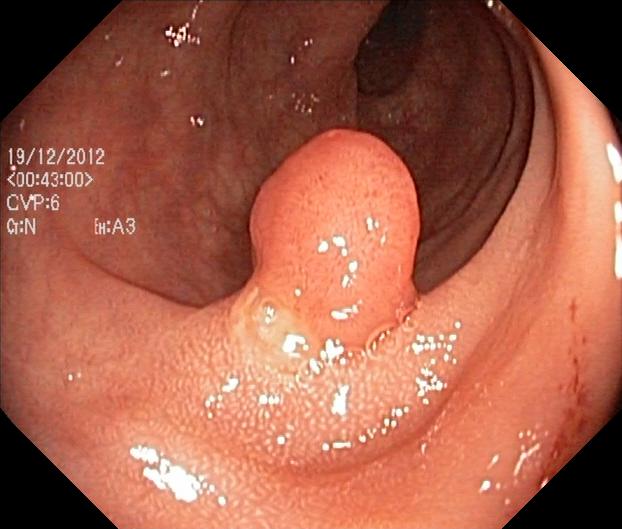

Test data: Kvasir-SEG

• 1000 images

• various sizes

• Each image contains 1 polyp

• Collected and annotated by medical professionals

Jha, Debesh, et al. "Kvasir-seg: A segmented polyp dataset." MultiMedia modeling: 26th international conference, MMM 2020, Daejeon, South Korea, January 5–8, 2020, proceedings, part II 26. Springer International Publishing, 2020.